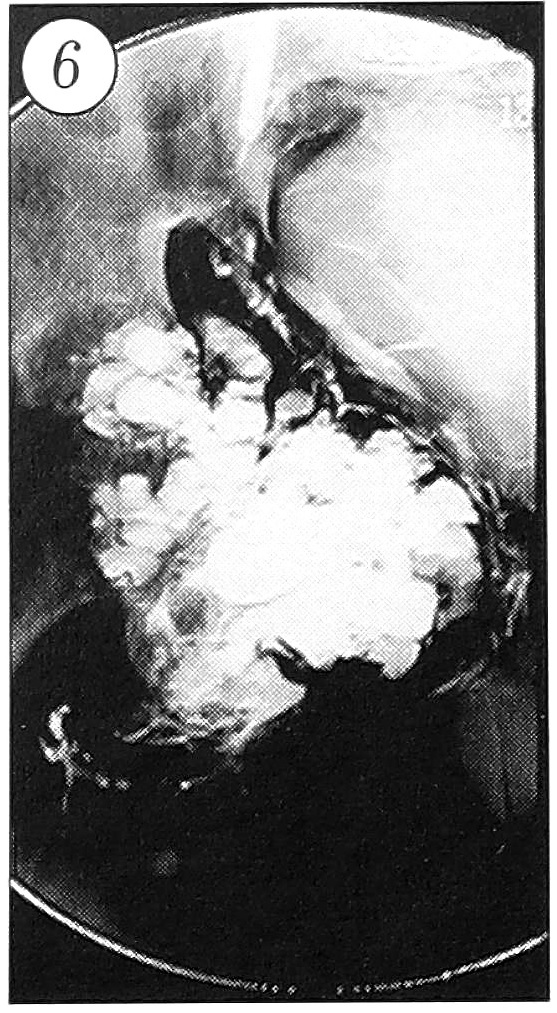

Произведена временная окклюзия внутренней подвздошной артерии баллонным катетером 6,0 × 30 мм (рис. 5). Повторно измерено внутрикистное давление — 500 мм вод. ст. (рис. 4, б). Для выявления возможного вовлечения в патологический процесс мочевого пузыря предпринято контрастирование очага омнипаком (20 мл): стенки пузыря оказались интактными (рис. 6).

Рис. 5. Окклюзия внутренней подвздошной артерии баллонным катетером.

Рис. 6. Контрастирование очага: мочевой пузырь интактен.